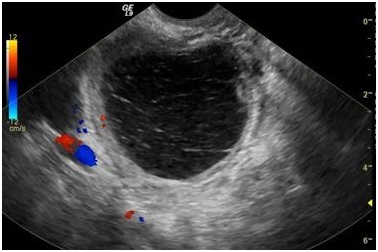

Так выглядит гиперэхогенное образование на экране УЗИ

- Гиперэхогенные. Большая сопротивляемость таких включений к прохождению звукового сигнала проявляется в виде светлых участков. Это включение обладает более плотной структурой, чем ткани матки.

Основным методом диагностики является ультразвуковое исследование (УЗИ) органов малого таза. УЗИ позволяет визуализировать матку и выявить наличие гиперэхогенных образований. Гиперэхогенные участки на УЗИ выглядят как светлые области, что указывает на их плотность и состав. Важно отметить, что гиперэхогенные образования могут быть как доброкачественными, так и злокачественными, поэтому дальнейшее обследование необходимо для уточнения диагноза.